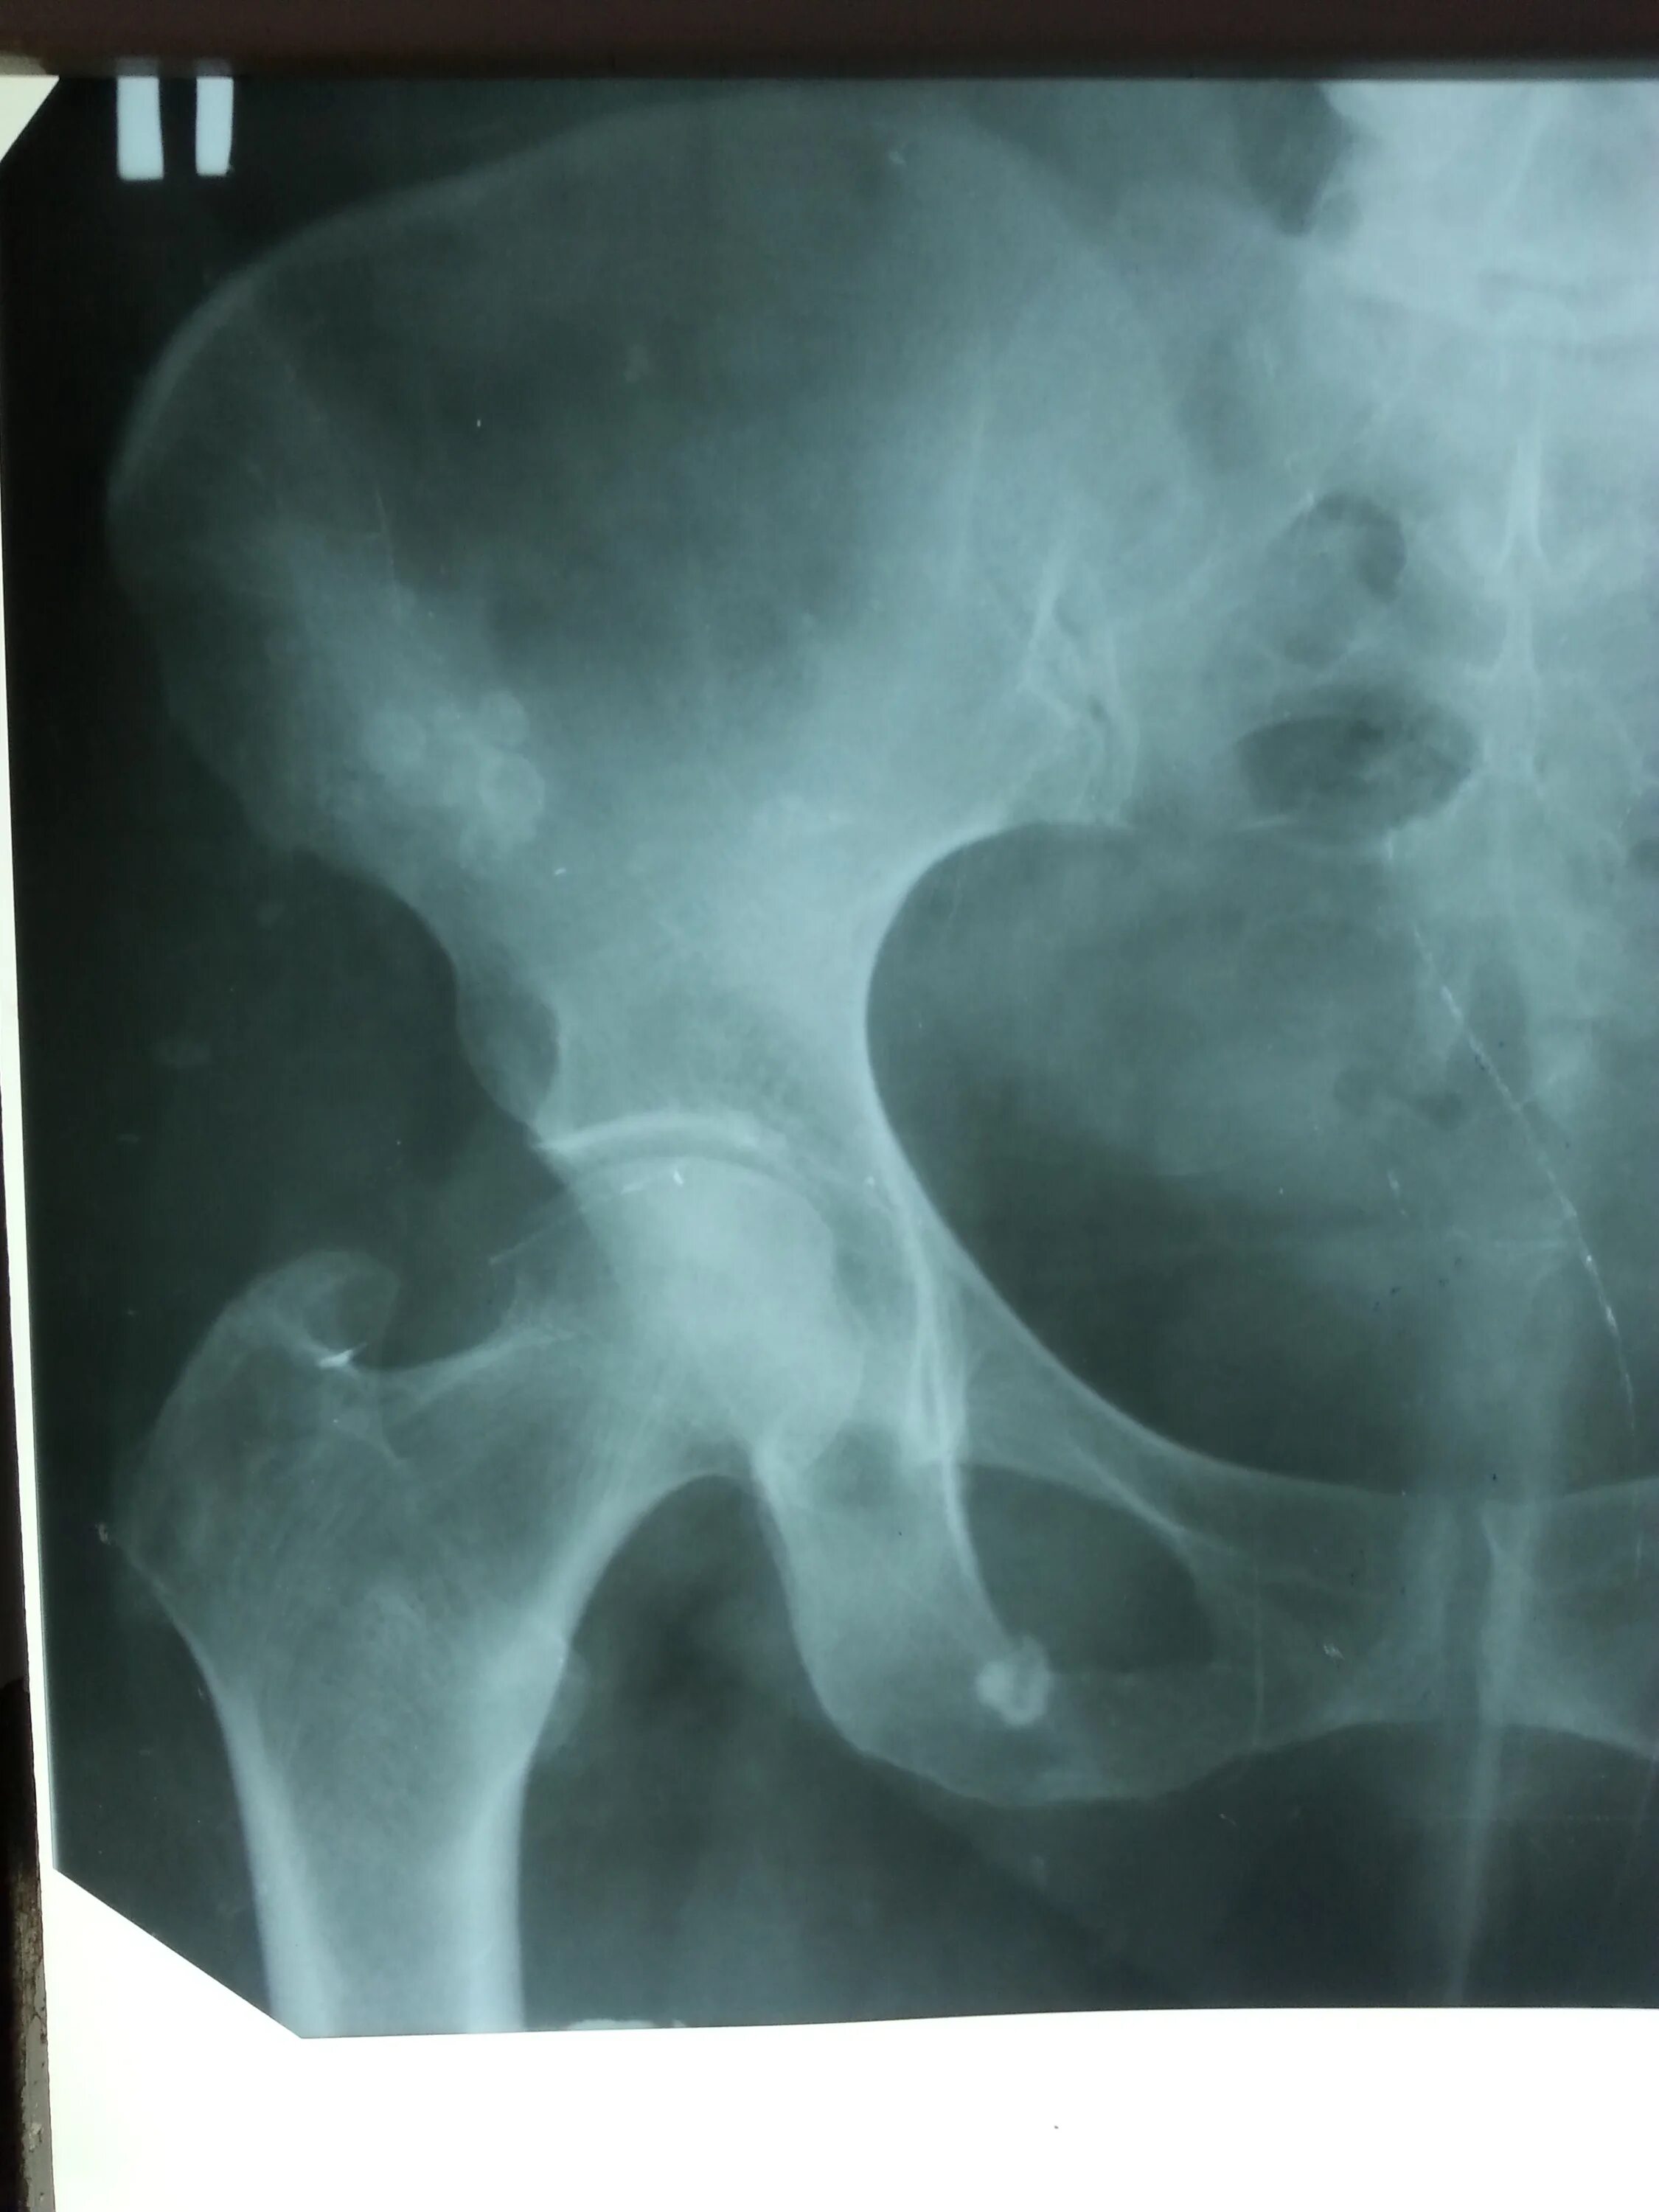

Метастазы в тазобедренном